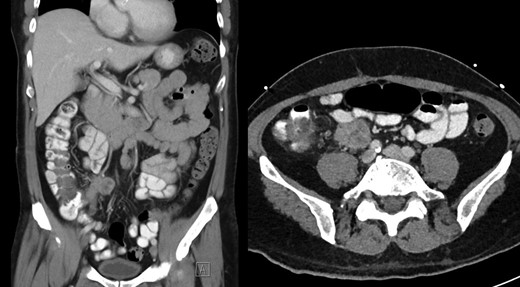

During this period he also developed osteolytic lesions of the T9/10 vertebral bodies immediately adjacent to the effusion (Fig. 1). Magnetic resonance imaging (MRI) was arranged showing T8–T10 spondylodiscitis, prevertebral and epidural phelgmons (Fig. 2), without radiological evidence of spinal cord compression. Further imaging with gallium scan showed no evidence of osteomyelitis elsewhere in the body, but unexpectedly revealed area of increased vascularity in the right iliac fossa suggestive of soft tissue infection. CT abdomen confirmed the lesion to be a peri-appendicular abscess (Fig. 3).

Post-contrast CT abdomen, showing peri-appendicular abscess corresponding to area of increased uptake on gallium scan.